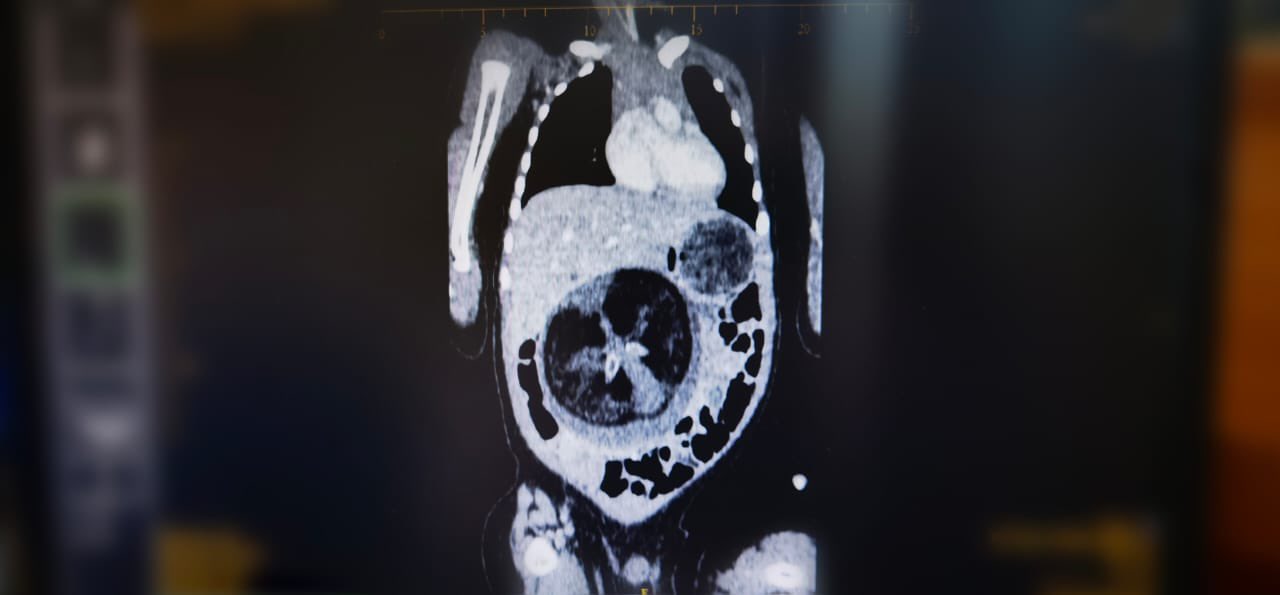

أجرى قسم جراحة الأطفال بالمستشفى السلطاني في سلطنة عمان عملية جراحية نادرة، تمثلت في استئصال جنين من داخل جنين لطفل يبلغ من العمر ثمانية أشهر، بحسب وزارة الصحة العمانية.

وقد أجريت العملية لطفل يبلغ من العمر ثمانية أشهر، بطاقم طبي ترأسه الدكتور محمد بن جعفر الساجواني، استشاري أول رئيس قسم جراحة الأطفال بالمستشفى السلطاني.

وتعرف هذه الظاهرة الطبية بـFetus in Feto، وتحدث بنسبة 1 بين كل 500 ألف حالة ولادة حية على مستوى العالم.